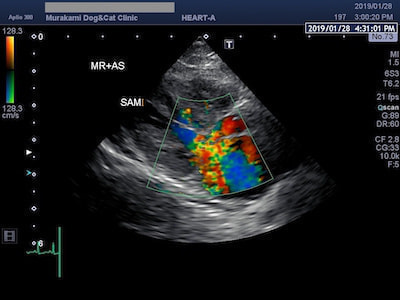

僧帽弁前尖収縮期前方運動(SAM)

HCMのなかには、僧帽弁前尖収縮期前方運動(SAM)と呼ばれる僧帽弁の異常な運動により、左心室から流出する血液の通路を妨害したり(左室流出路閉塞)、異常な弁の動きにより僧帽弁逆流を伴うものがあります。このようなHCMは閉塞性肥大型心筋症(HOCM)と呼ばれています。

SAMによる僧帽弁逆流

閉塞性肥大型心筋症(HOCM)は、SAMによる左室流出路閉塞と僧帽弁逆流を伴うため、左心房圧が上昇し肺水腫や血栓症のリスクが高まります。治療には血管を拡げて心臓の負担をとるための血管拡張薬や、尿を出して鬱血を改善するための利尿剤、血栓予防のお薬などを使います。